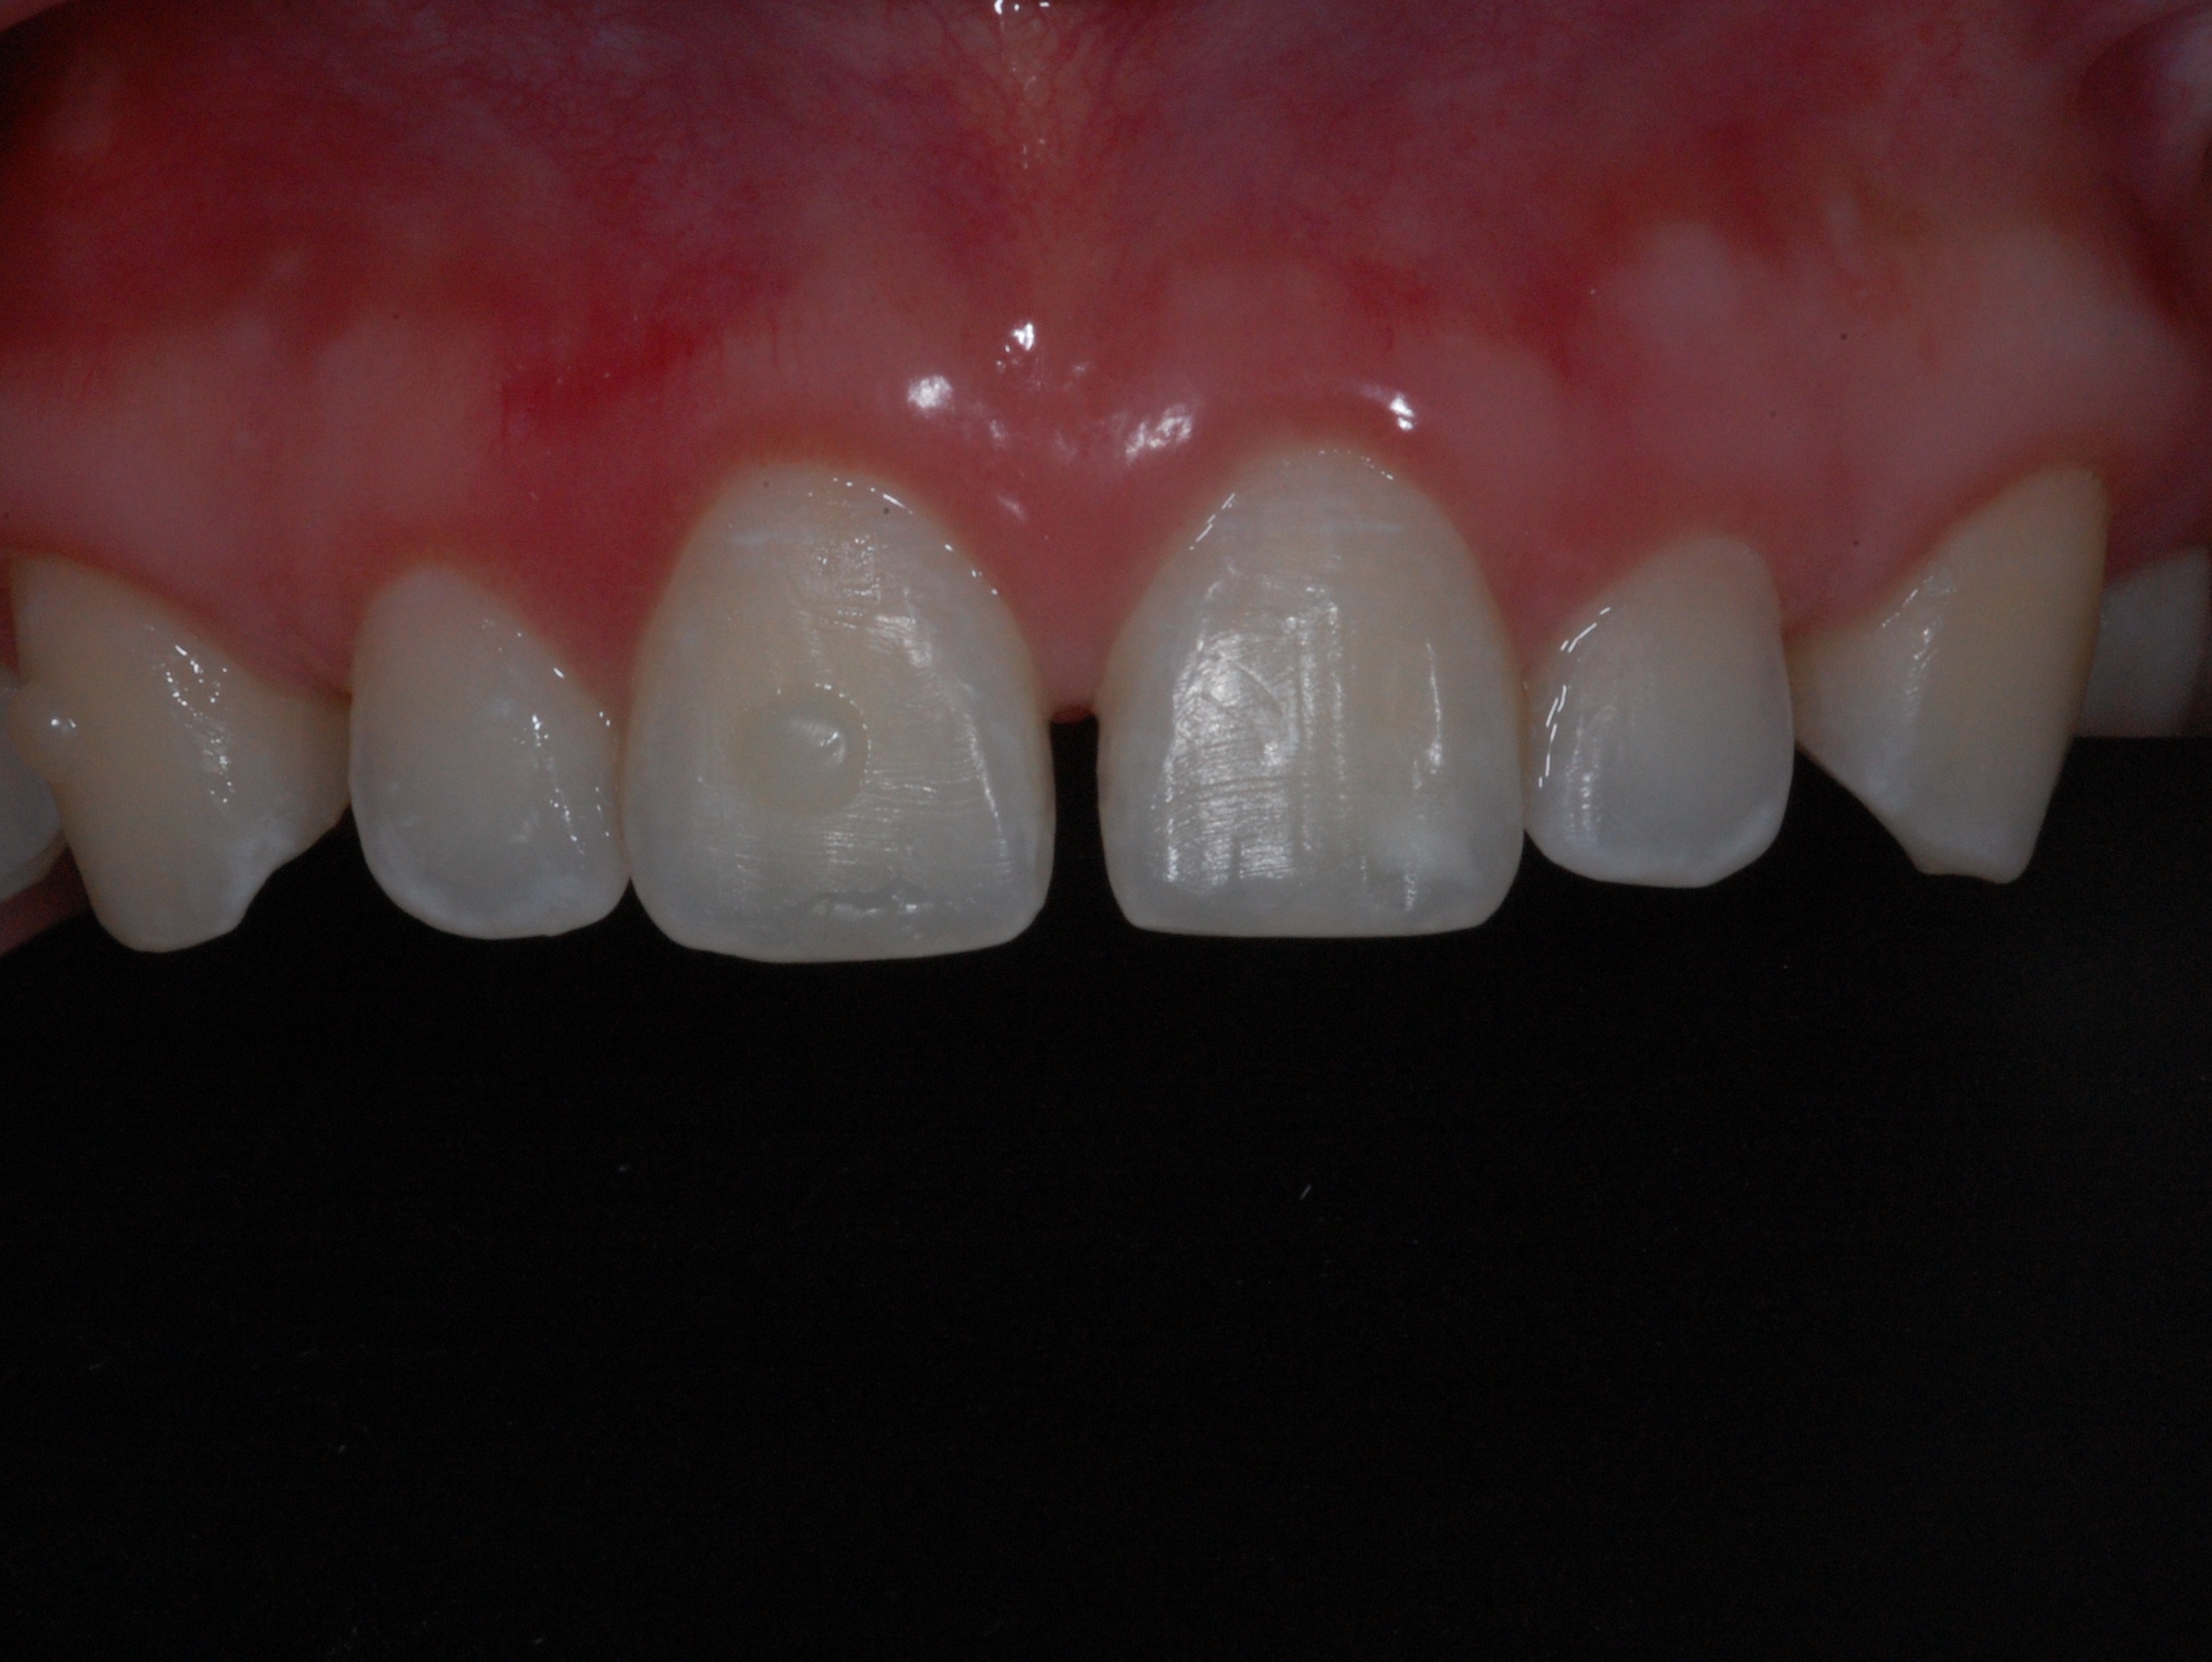

The presence of diastema, between anterior teeth, distorts a pleasing smile by concentrating the observer’s attention on the spaces. The patient’s needs and expectations must be considered in the process of treatment planning to ensure satisfaction with the treatment outcomes. There are many forms of therapy that can be used for diastema closure. A carefully developed diagnosis, which includes a determination of the causal elements and advanced treatment planning, allows the most appropriate treatment to be selected for each case. The aim of this paper is present a multidisciplinary approach as a solution to multiple diastemas in the anterior region using gingival tissue recontouring and direct adhesive restorations, with minimum wear of the dental structure, after the orthodontic intervention discussing the minimal intervention to obtain imperceptive and aesthetic final restoration. Thirty-six months after the treatment was carried out, the final aesthetic was maintained with all dental element details and gingival tissue harmony, without recurrence of periodontal pockets and the preservation of the tooth color and shape.